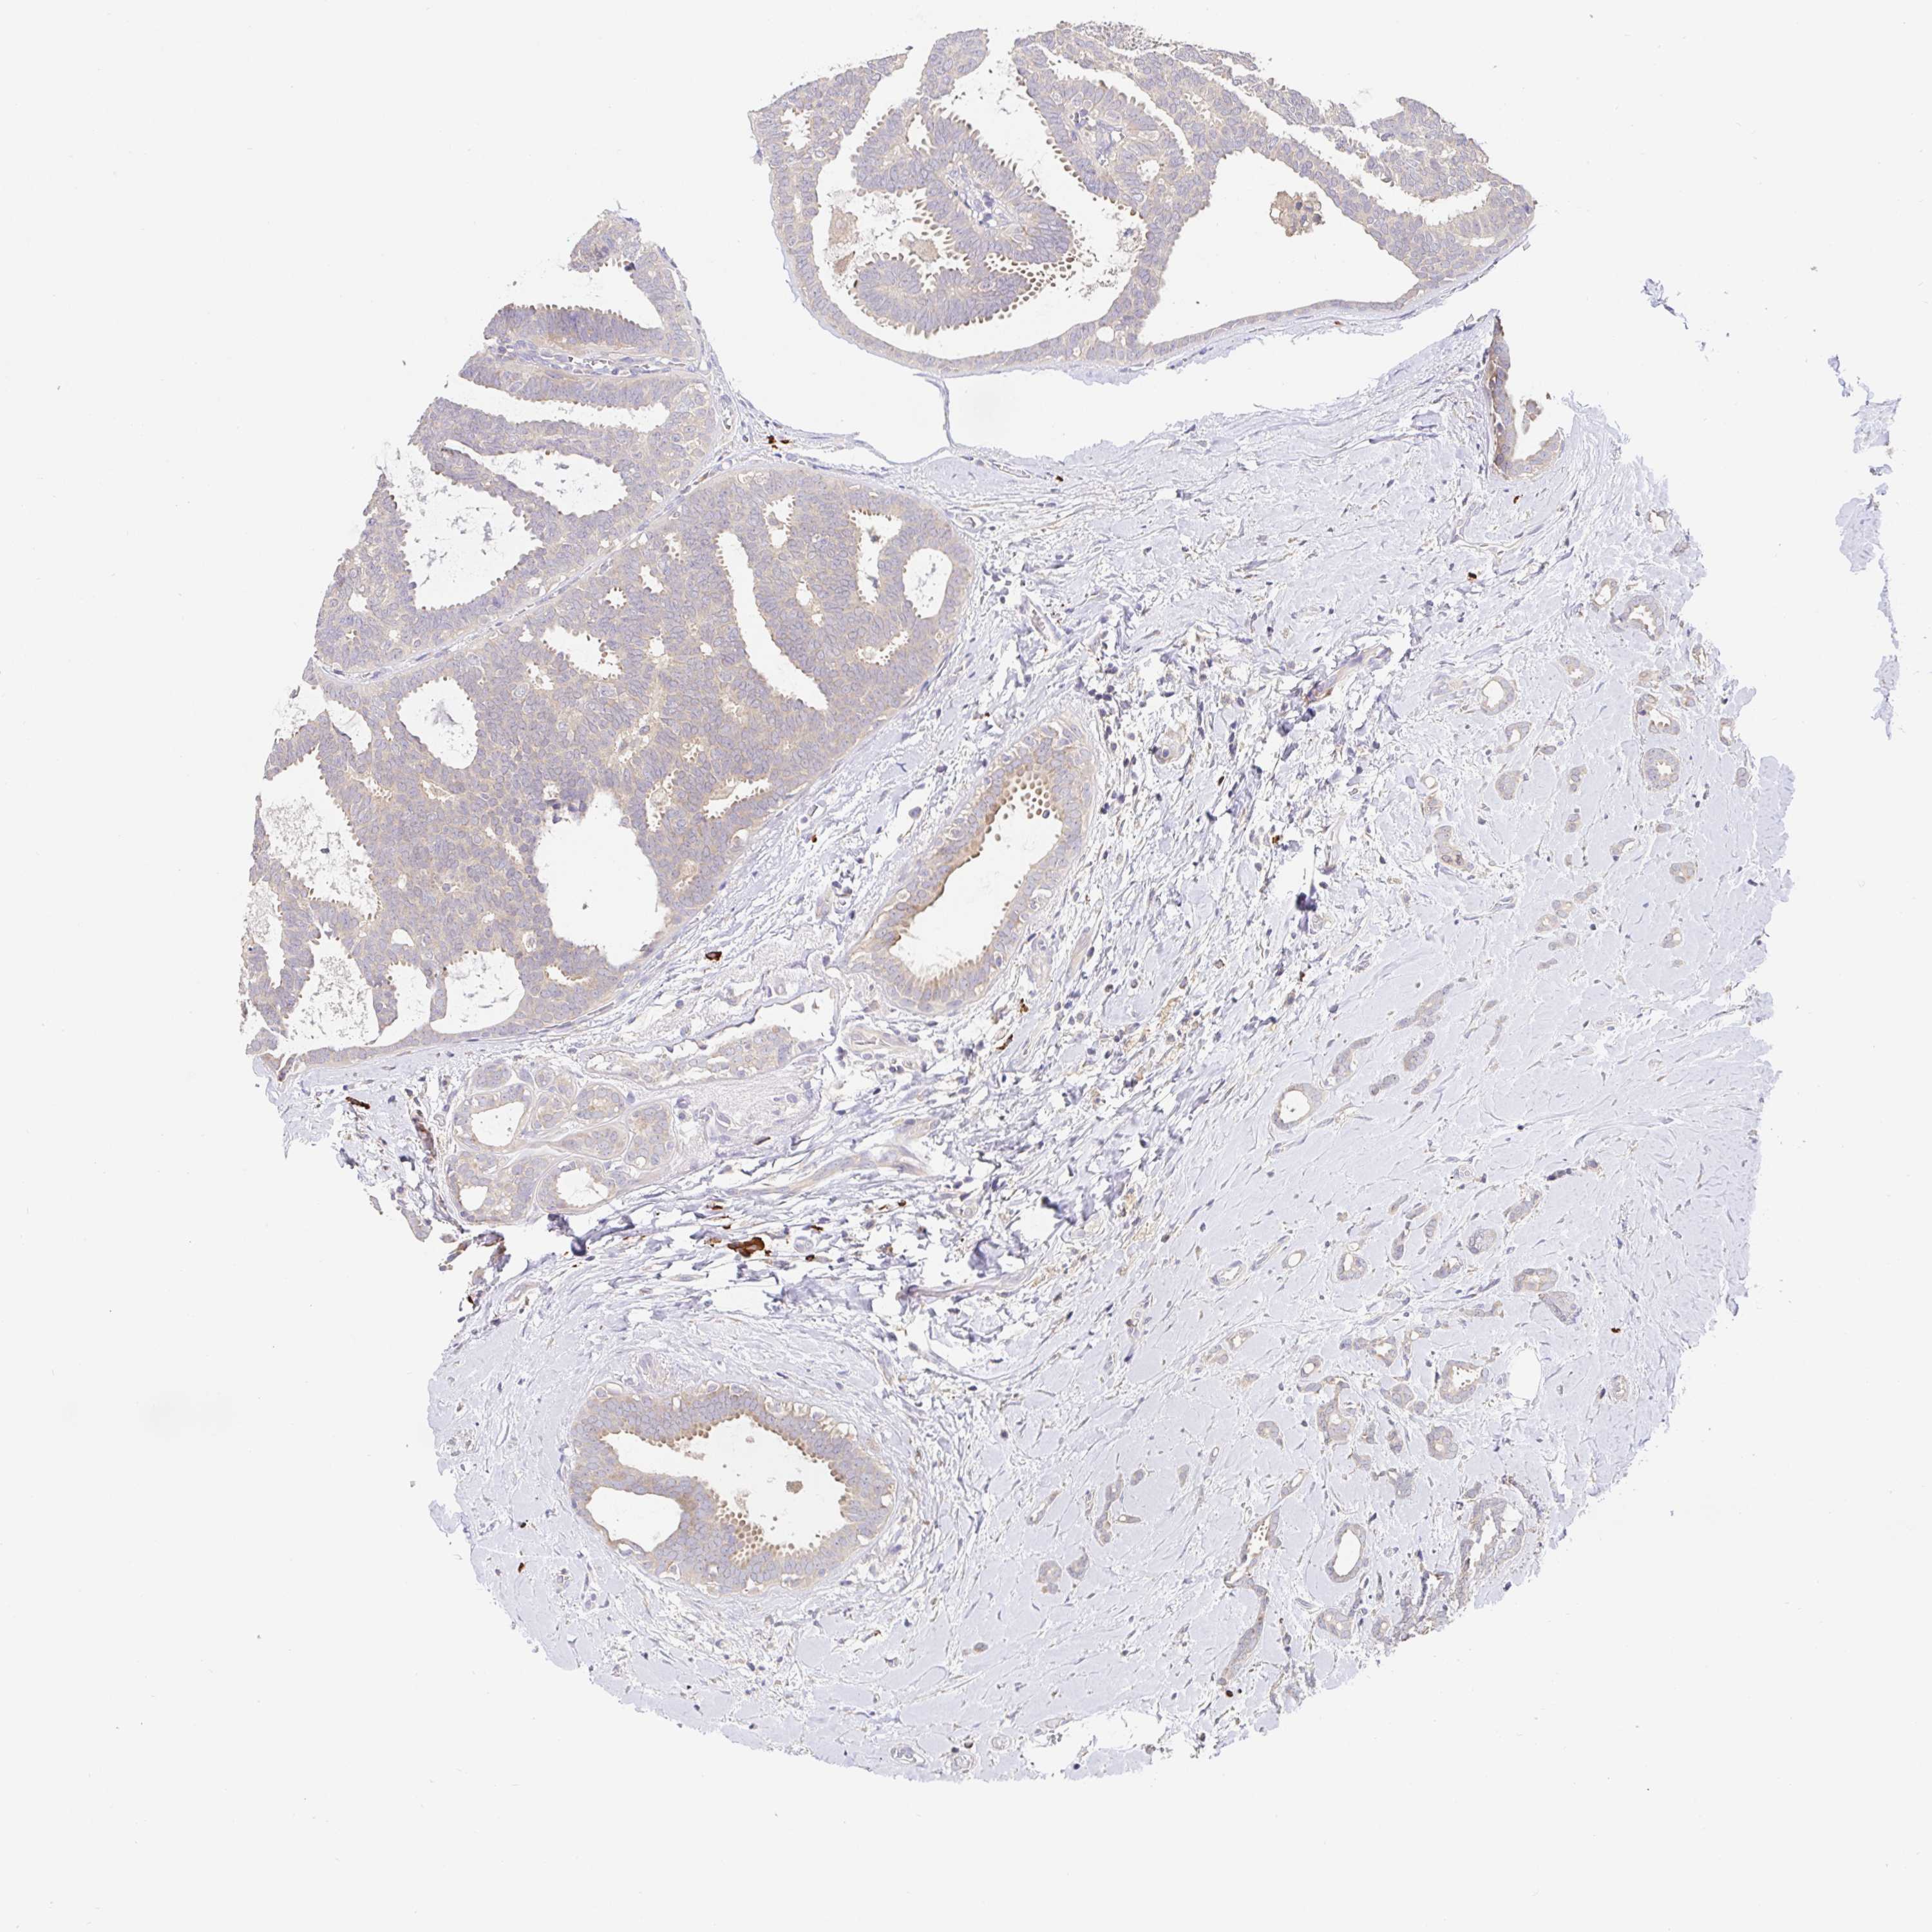

CANCER BREAST CANCER Show tissue menu

BRCA TCGA BRCA VALIDATION PROTEIN EXPRESSION